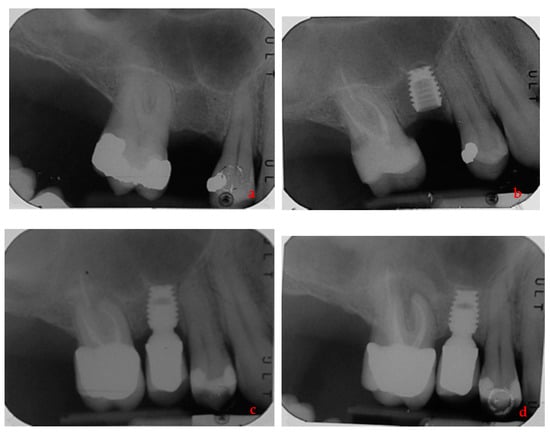

- Lombardo, G.; Signoriello, A.; Simancas-Pallares, M.; Marincola, M.; Nocini, P.F. Survival of Short and Ultra-Short Locking-Taper Implants Supporting Single Crowns in the Posterior Mandible: A 3-Year Retrospective Study. J. Oral Implant. 2020, 46, 396–406. [Google Scholar] [CrossRef] [PubMed]

- Lombardo, G.; Marincola, M.; Signoriello, A.; Corrocher, G.; Nocini, P.F. Single-Crown, Short and Ultra-Short Implants, in Association with Simultaneous Internal Sinus Lift in the Atrophic Posterior Maxilla: A Three-Year Retrospective Study. Materials 2020, 13, 2208. [Google Scholar] [CrossRef] [PubMed]